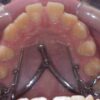

さて,医療で最も精度を必要とするのは実は口の中です.噛み合わせというのは髪の毛一本挟まっていてもわかるくらい繊細なものですし,被せや詰め物は,細菌が入り込む余地を許さない精度でないと,そこからまた虫歯や歯周病になってしまいます.

そのような精度で治療できるように,歯科医はあらゆる努力をしています.イースマイルの患者さんも連携治療でよくお世話になっている富塚歯科医院の技工室に先日お邪魔しましたが,非常に精度の高い,全くガタツキのない技工物の制作途中を見せて頂きました.こうした極めて精度の高い補綴物は,セットしたときに噛み合わせの調整すら必要ないくらいだそうです.